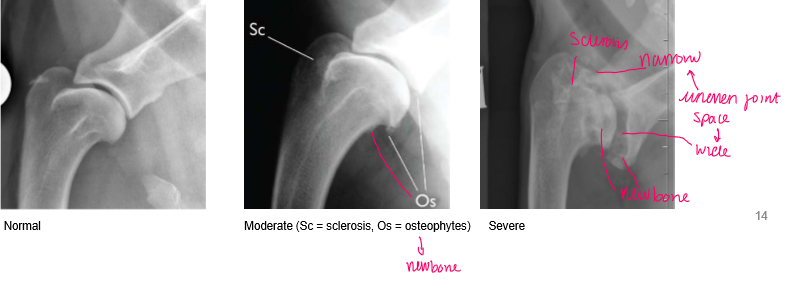

What will be seen in chronic shoulder arthrosis?

Lots of new bone (osteophytes)

Underlying cause often not evident

label the normal

sclerosis and osteophytes

sclerosis, uneven joint space, osteophytes (New bone)

WHAT do we expect to see at normal joint

nicely rounded and smooth margin to the

head of the humerus and look at the margins of

the distal part of the scapula spine and the joint

space here.

So nice and smooth and nice.